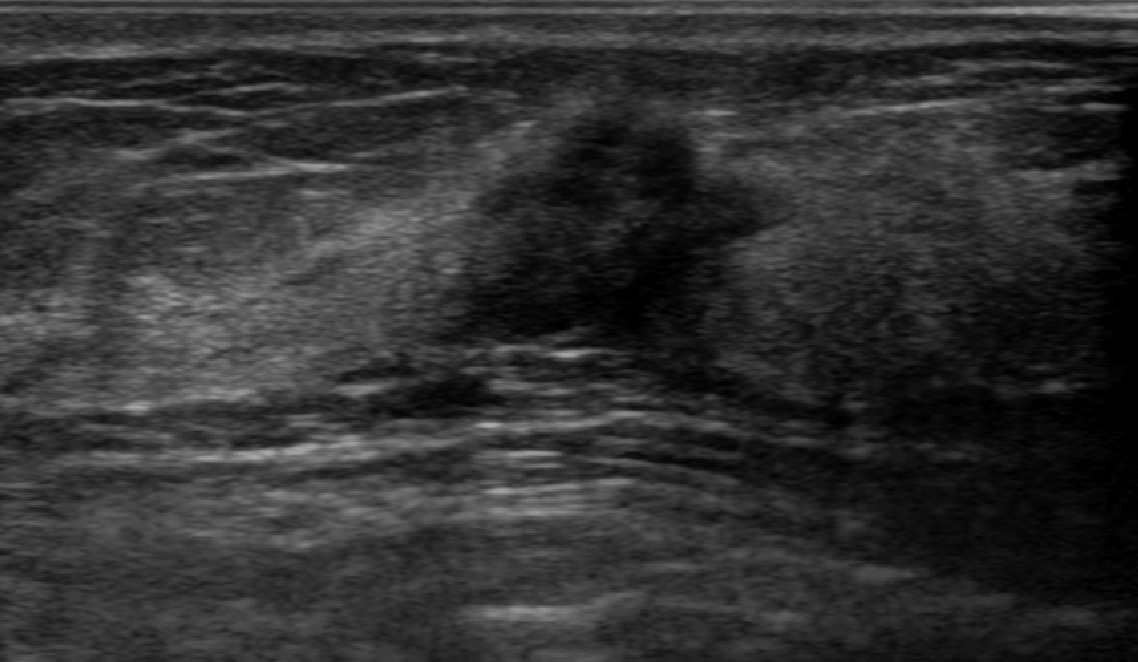

Ultrasonography is an important routine examination for breast cancer diagnosis, due to its non-invasive, radiation-free and low-cost properties. However, it is still not the first-line screening test for breast cancer due to its inherent limitations. It would be a tremendous success if we can precisely diagnose breast cancer by breast ultrasound images (BUS). Many learning-based computer-aided diagnostic methods have been proposed to achieve breast cancer diagnosis/lesion classification. However, most of them require a pre-define ROI and then classify the lesion inside the ROI. Conventional classification backbones, such as VGG16 and ResNet50, can achieve promising classification results with no ROI requirement. But these models lack interpretability, thus restricting their use in clinical practice. In this study, we propose a novel ROI-free model for breast cancer diagnosis in ultrasound images with interpretable feature representations. We leverage the anatomical prior knowledge that malignant and benign tumors have different spatial relationships between different tissue layers, and propose a HoVer-Transformer to formulate this prior knowledge. The proposed HoVer-Trans block extracts the inter- and intra-layer spatial information horizontally and vertically. We conduct and release an open dataset GDPH&GYFYY for breast cancer diagnosis in BUS. The proposed model is evaluated in three datasets by comparing with four CNN-based models and two vision transformer models via a five-fold cross validation. It achieves state-of-the-art classification performance with the best model interpretability.

翻译:超声波分析是乳腺癌诊断的一个重要常规检查,原因是其非侵入性、无辐射和低成本的特性。然而,由于其内在局限性,它仍不是乳腺癌的第一线筛选测试。如果我们能够精确地通过乳房超声图像诊断乳腺癌(BUS),它将是一个巨大的成功。我们提出了许多基于学习的计算机辅助诊断方法,以实现乳腺癌诊断/感官分类。然而,其中多数方法需要事先确定性能模型,然后对ROI内部的跨值进行分类。常规分类支柱,如VGG16和ResNet50等,可以在没有ROI要求的情况下实现有希望的分类结果。但是这些模型缺乏可解释性,从而限制了其在临床实践中的使用。在本研究中,我们提出了一个新的无乳腺癌诊断模型,在超声波图像中进行解释性特征描述。我们利用了先前的解剖学学学知识,即恶性肿瘤和良性肿瘤模型在不同组织层之间有着不同的空间关系,并提议采用状态解析法来编制这一先前的知识。拟议中的HOVer-Trans-Trading-Tradef-trainal Ex-deal-dealal-deal-deal-deal-degraphal-deal-deal-deal-deal-deal-deal disal disal-dal-dal-dal-dal-dal-deal-deal-dal-deal-deal-deal-dal-dal-dal-dal-dal-dal-dal-dal-dal-dal-dal-dal-dal-dal-I-dal-Iversal-dal-Ial-d-d-I-d-d-I-I-I-I-I-I-I-I-I-I-I-I-I-I-I-I-I-I-I-I-I-I-I-I-I-Ial-I-Ial-Ial-I-I-I-I-I-I-I-I-I-I-I-I-I-I-I-I-I-I-I-I-I-I-I-I-I-I-I-I-I-I-I-I-